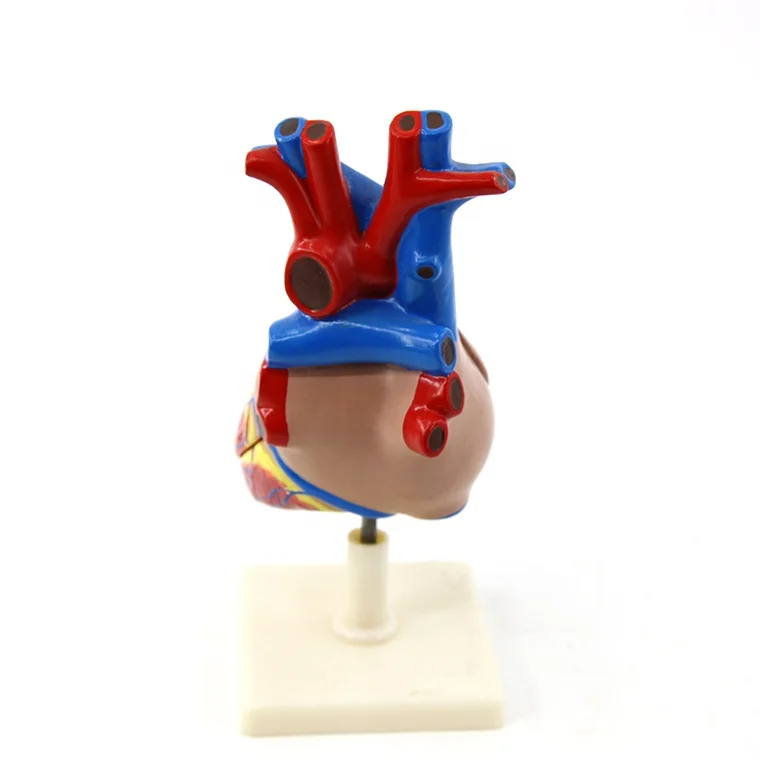

Valentine’s Day ช็อกโกแลตหัวใจ 12 ชิ้น – ของขวัญรังนกแท้ คอซซี่ โมเดลหัวใจมนุษย์ (Human Heart) | Shopee Thailand

โมเดลหัวใจมนุษย์ (Human Heart) | Shopee Thailand หัวใจมนุษย์ ภาพสต็อก – ดาวน์โหลดรูปภาพตอนนี้ – หัวใจ – อวัยวะภายใน …

ขยายกายวิภาคหัวใจมนุษย์รุ่น 3 ชิ้นส่วน – Buy กายวิภาคหัวใจ,หัวใจ … หัวใจมนุษย์ การออกแบบรายละเอียด ภาพประกอบสต็อก – ดาวน์โหลดรูปภาพตอนนี้ …

ชีวิตพลาสติกกายวิภาคหัวใจมนุษย์รุ่น2ชิ้นส่วน – Buy การสอนรุ่น,Anatomy … ช็อคโกแลตรูปหัวใจ [ภาพวาดฟรี] | OkusanPix

ชีวิตพลาสติกกายวิภาคหัวใจมนุษย์รุ่น2ชิ้นส่วน – Buy การสอนรุ่น,Anatomy … ขนมช็อกโกแลตแท่ง ตรา โชกี้ โชกี้ 1 บาท แพ็ค 100 ชิ้น | Shopee Thailand

ขนมช็อกโกแลตแท่ง ตรา โชกี้ โชกี้ 1 บาท แพ็ค 100 ชิ้น | Shopee Thailand ชีวิตพลาสติกกายวิภาคหัวใจมนุษย์รุ่น2ชิ้นส่วน – Buy การสอนรุ่น,Anatomy …

ชีวิตพลาสติกกายวิภาคหัวใจมนุษย์รุ่น2ชิ้นส่วน – Buy การสอนรุ่น,Anatomy … รักสุดใจ! ช่อช็อกโกแลตให้เธอ รวมไอเดียช่อช็อกโกแลตสื่อรัก มอบให้แฟน

In-306 3d กายวิภาคศาสตร์หัวใจมนุษย์รูปแบบทางการแพทย์พลาสติกกายวิภาค … หัวใจมนุษย์ ภาพสต็อก – ดาวน์โหลดรูปภาพตอนนี้ – หัวใจ – อวัยวะภายใน, การ …

หัวใจวิทยาศาสตร์เรื่องกายวิภาคศาสตร์ทางการแพทย์หัวใจมนุษย์รุ่นขาย – Buy … หัวใจวิทยาศาสตร์เรื่องกายวิภาคศาสตร์ทางการแพทย์หัวใจมนุษย์รุ่นขาย – Buy …

หัวใจวิทยาศาสตร์เรื่องกายวิภาคศาสตร์ทางการแพทย์หัวใจมนุษย์รุ่นขาย – Buy … Anatomy หัวใจมนุษย์รุ่นพลาสติกทางการแพทย์กายวิภาคหัวใจจัมโบ้รุ่นอวัยวะ …

Anatomy หัวใจมนุษย์รุ่นพลาสติกทางการแพทย์กายวิภาคหัวใจจัมโบ้รุ่นอวัยวะ … รูปช็อกโกแลตหัวใจพร้อมน้ำเชื่อม PNG , วาเลนไทน์วัน, หัวใจ, วันแห่งความ …

3d Anatomy หัวใจมนุษย์รุ่นพลาสติกทางการแพทย์กายวิภาคหัวใจจัมโบ้รุ่น … หัวใจวิทยาศาสตร์เรื่องกายวิภาคศาสตร์ทางการแพทย์หัวใจมนุษย์รุ่นขาย – Buy …

หัวใจวิทยาศาสตร์เรื่องกายวิภาคศาสตร์ทางการแพทย์หัวใจมนุษย์รุ่นขาย – Buy … ส่งไว🚀24ชม. เจบีช็อกโกแลต รูปฟุตบอล เหรียญทอง เหรียญเงิน ทองแท่ง หัวใจ …

Anatomy หัวใจมนุษย์รุ่นพลาสติกทางการแพทย์กายวิภาคหัวใจจัมโบ้รุ่นอวัยวะ … ภาพประกอบแบนเวกเตอร์หัวใจมนุษย์ขนาดใหญ่บนพื้นหลังสีขาว ภาพประกอบสต็อก …

หัวใจมนุษย์กายวิภาครุ่นวิทยาศาสตร์การแพทย์รูปแบบการสอน ห้องหัวใจมนุษย์: คำอธิบายโครงสร้างหน้าที่และประเภท

หุ่นจำลองหัวใจมนุษย์ 3d มนุษย์กายวิภาครุ่นหัวใจมนุษย์สำหรับซัพพลายเออร์แบบครบวงจรวิทยาศาสตร์ …

3d มนุษย์กายวิภาครุ่นหัวใจมนุษย์สำหรับซัพพลายเออร์แบบครบวงจรวิทยาศาสตร์ … 3d Anatomy หัวใจมนุษย์รุ่นพลาสติกทางการแพทย์กายวิภาคหัวใจจัมโบ้รุ่น …

3d Anatomy หัวใจมนุษย์รุ่นพลาสติกทางการแพทย์กายวิภาคหัวใจจัมโบ้รุ่น … อวัยวะหัวใจของมนุษย์ | องค์ประกอบกราฟฟิก แบบ PSD ดาวน์โหลดฟรี – Pikbest

หัวใจมนุษย์กายวิภาครุ่นวิทยาศาสตร์การแพทย์รูปแบบการสอน 15 Porch ช็อกโกแลต Fudge แม่พิมพ์ซิลิโคนหัวใจรูปเค้กช็อกโกแลตตกแต่ง DIY …

อุปกรณ์การศึกษากายวิภาคศาสตร์รุ่นหัวใจมนุษย์รุ่นสำหรับโรงเรียนขนาดชีวิต … วิธีทำ “นามะช็อกโกแลต” ของฝากยอดฮิตจากญี่ปุ่น อร่อยหรูดูแพง แต่ทำง่าย …

In-306 3d กายวิภาคศาสตร์หัวใจมนุษย์รูปแบบทางการแพทย์พลาสติกกายวิภาค … บอลลูนหัวใจมนุษย์ Angioplasty เวกเตอร์ ภาพประกอบ ภาพประกอบสต็อก – ดาวน์ …

โรงงานโดยตรงขาย Anatomy หัวใจมนุษย์การฝึกอบรมชุดอวัยวะภายในรุ่น – Buy …